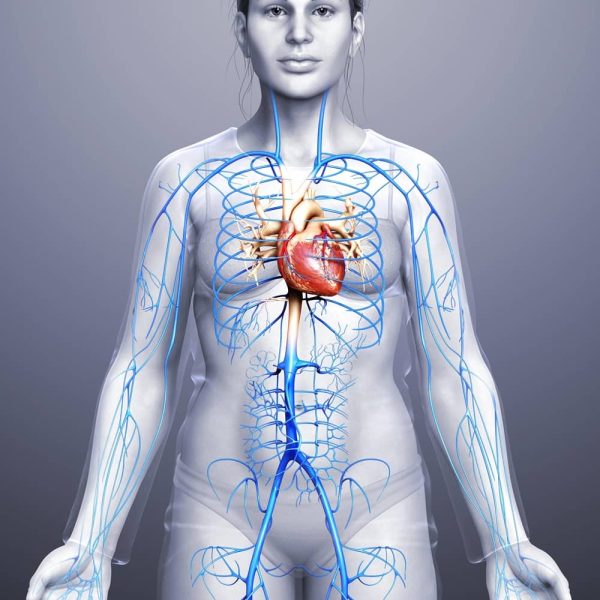

محل دقیق قلب در زنان، تفاوت اساسی با محل آن در مردان ندارد و در هر دو جنس در یک مکان یکسان قرار گرفته است. باور عمومی مبنی بر اینکه قلب کاملاً در سمت چپ بدن قرار دارد، دقیق نیست. در واقع، قلب در مرکز قفسه سینه، در فضایی به نام مدیاستینوم (Mediastinum) که بین دو ریه قرار دارد، واقع شده است.

-موقعیت مرکزی: قلب در وسط قفسه سینه، درست پشت استخوان جناغ (Sternum) قرار دارد.

-تمایل به چپ: با اینکه قلب در مرکز است، اما بخش بزرگتر و قویتر آن (حدود دو سوم حجم قلب، به ویژه بطن چپ) به سمت چپ بدن متمایل شده است. به همین دلیل است که ما ضربان قلب را به وضوح در سمت چپ قفسه سینه خود احساس میکنیم.

-بین ریهها: قلب توسط ریه راست و چپ احاطه شده است.

-بالای دیافراگم: قلب روی عضله دیافراگم که قفسه سینه را از حفره شکمی جدا میکند، قرار گرفته است.

-جلوی ستون مهرهها: این عضو حیاتی در جلوی مری و ستون مهرهها قرار دارد و توسط قفسه سینه محافظت میشود.

به طور خلاصه، قلب شما به عنوان یک زن، در مرکز قفسه سینه و کمی متمایل به چپ قرار دارد، دقیقاً همان جایی که در بدن مردان نیز یافت میشود.